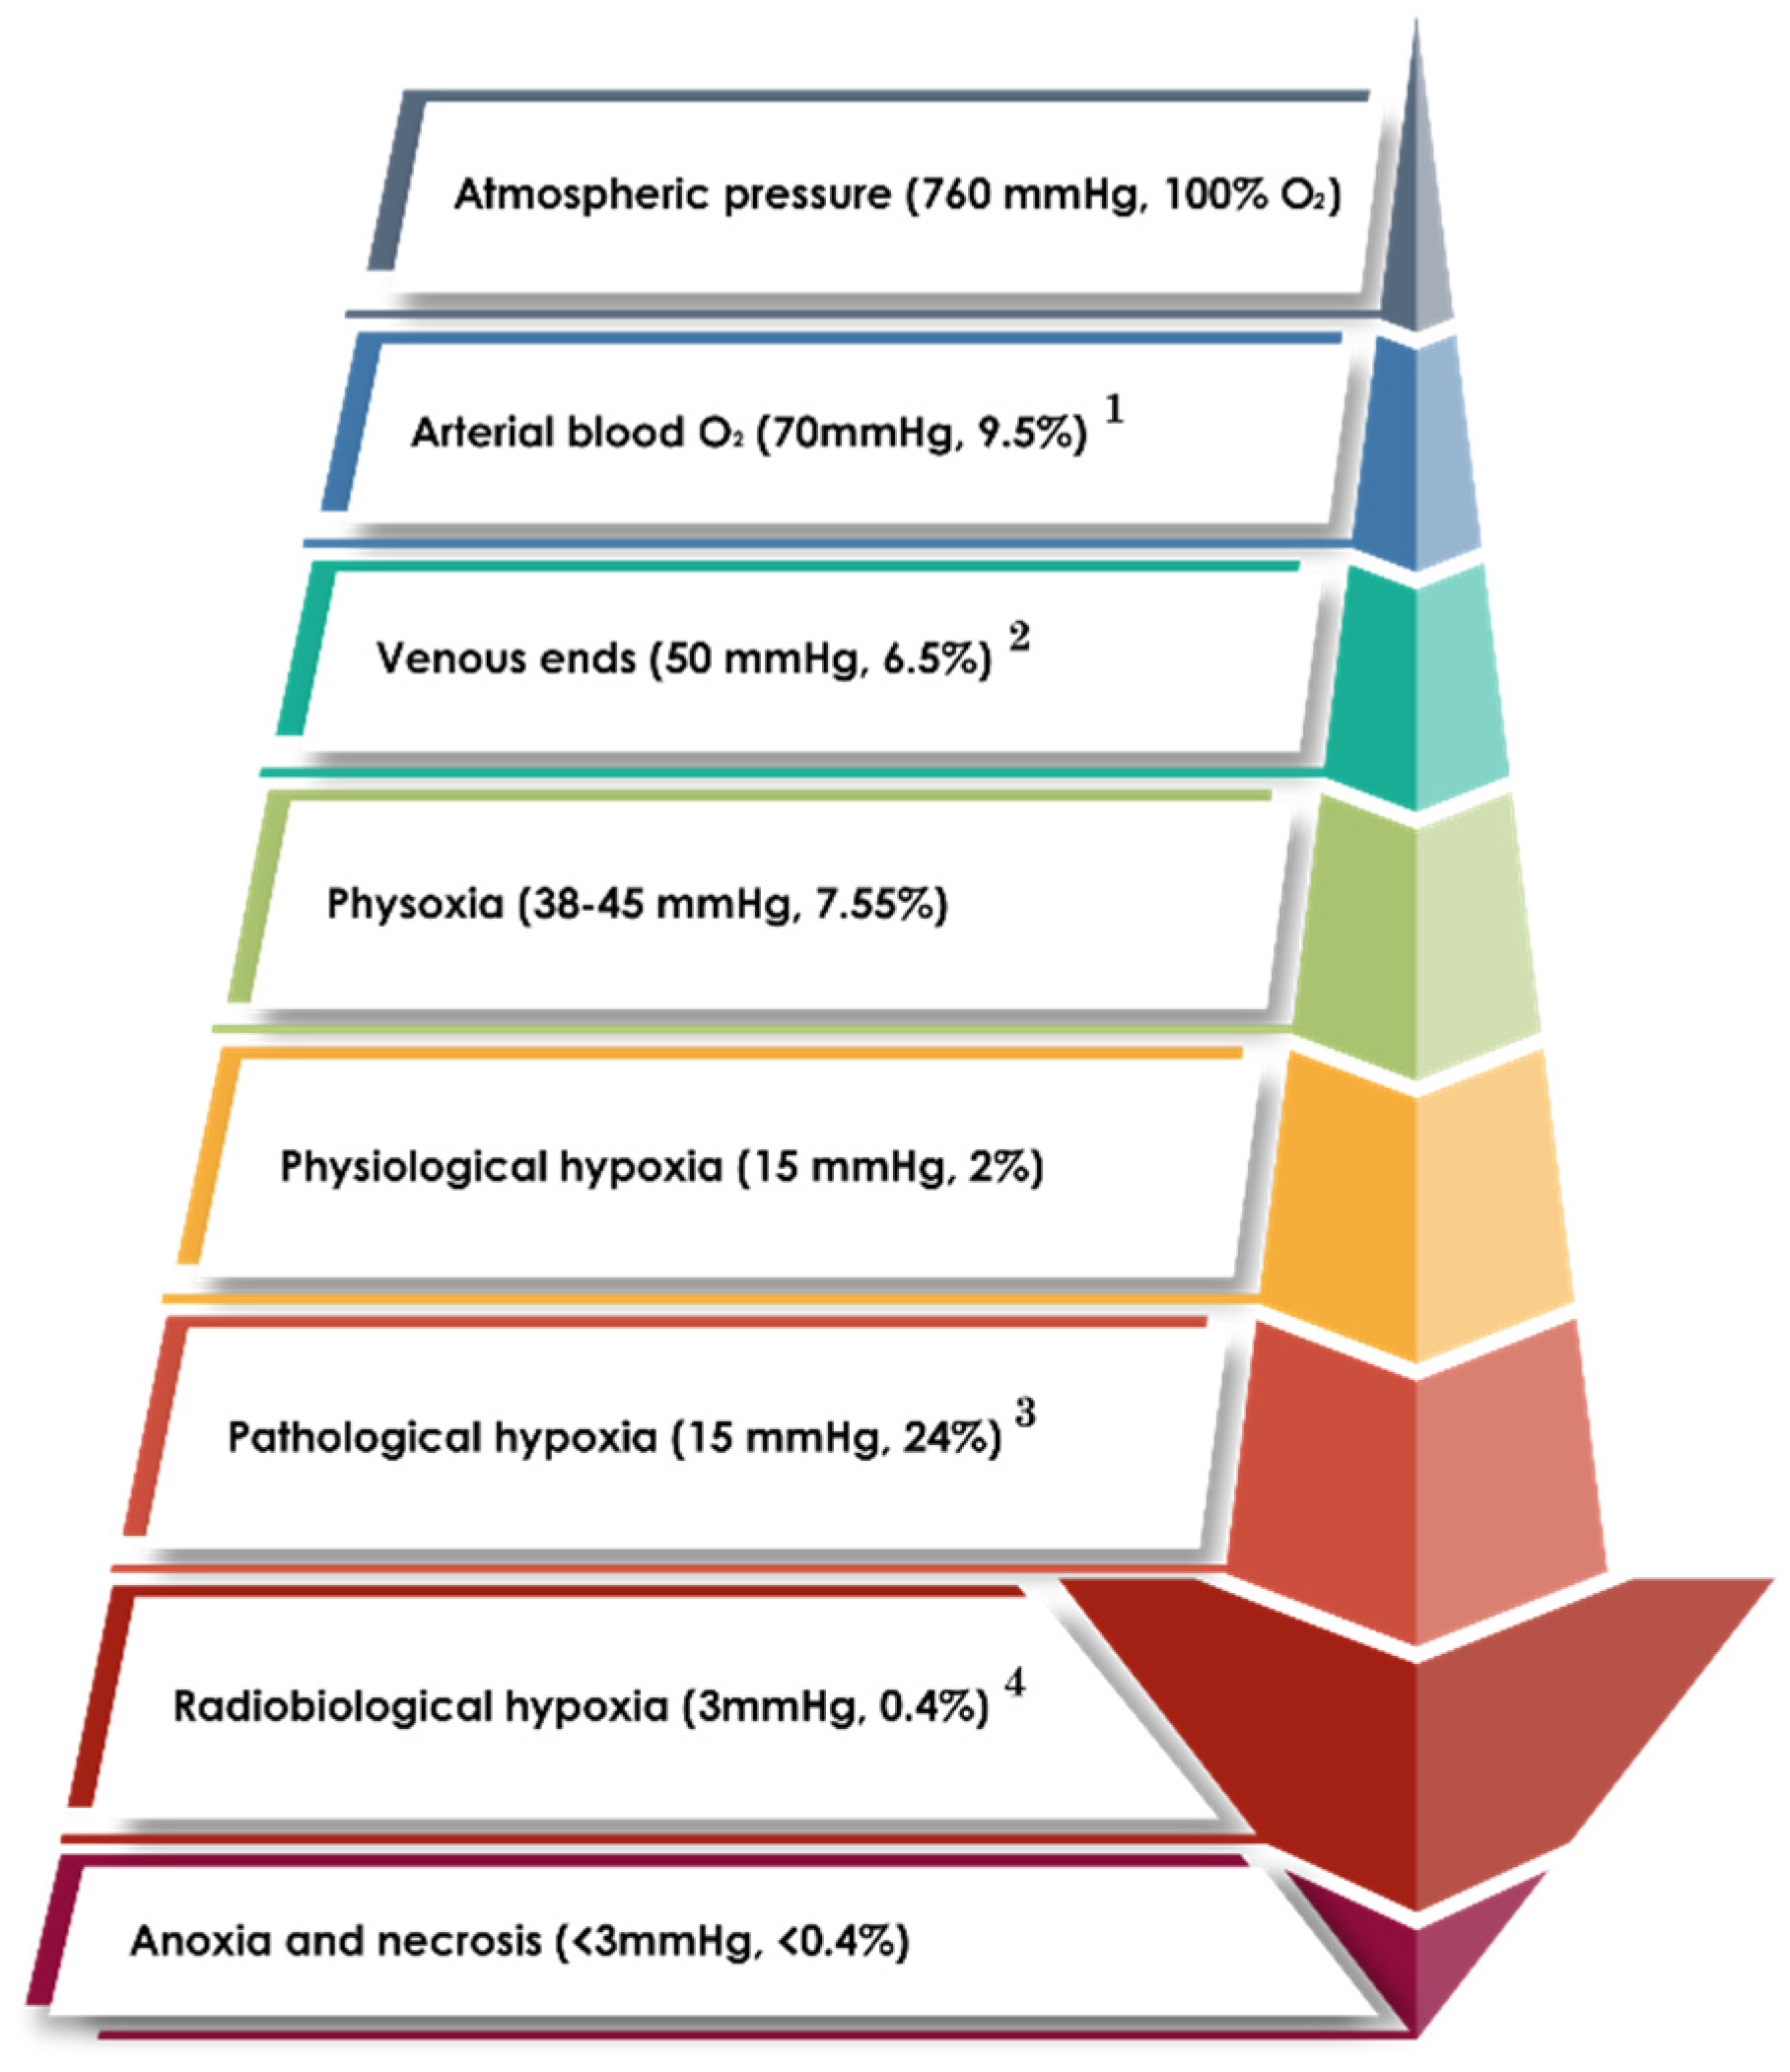

2. Pathophysiology of Hypoxia